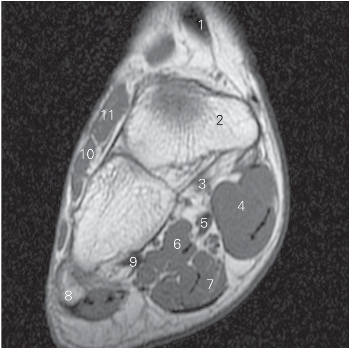

图5-47 经距骨颈的横断层MR T1加权图像

1 胫骨 tibia 2 踝关节 ankle joint

3 胫舟韧带 ligamenta tibionaviculare

4 胫骨后肌 tibialis posterior 5 舟骨 navicular bone

6

长屈肌 flexor hallucis longus 7

展肌 abductor hallucis

8 足底方肌 quadratus plantae 9 趾短屈肌 flexor digitorum brevis

10 腓骨短肌 peroneus brevis 11 跟骨 calcaneus

12 趾短伸肌 extensor digitorum brevis 13 距骨颈 neck of talus

14 腓骨短肌 peroneus brevis

15 趾长伸肌 extensor digitorum longus

图5-48 经距骨前份的横断层MR T1加权图像

1

长伸肌 extensor hallucis longus 2 距骨 talus

3 趾长屈肌 flexor digitorum longus 4

5

长屈肌 flexor hallucis longus 6 趾短屈肌 flexor digitorum brevis

7 小趾展肌 little toe abductor 8 足底方肌 quadratus plantae

9 腓骨短肌 peroneus brevis

10 趾长伸肌 extensor digitorum longus

图5-49 经第五跖骨近端的横断层MR T1加权图像

长伸肌腱 tendon of extensor hallucis longus

2 舟骨 navicular bone 3 趾长屈肌 flexor digitorum longus

4

展肌 abductor hallucis 5

长屈肌 flexor hallucis longus

6 足底方肌 quadratus plantae 7 趾短屈肌 flexor digitorum brevis

8 第五跖骨 5th metatarsal bone 9 腓骨长肌 peroneus longus

10 趾短伸肌 extensor digitorum brevis

11

短伸肌 extensor hallucis brevis